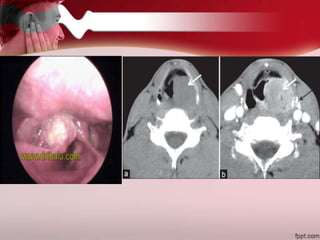

 Progressive infection of meatus, surrounding

soft tissue and skull base

 Causative Organism

 Pseudomonas auroginosa

 Predisposing Factors

 Elderly diabetics

 Immunocompromised

 Clinical Features

 Excruciating Pain

 Granulations in the Ext ear canal

 XII nerve palsy

 Treatment

 High doses I/V Antibiotics for

6-8 weeks

 Diabetic control

 Debridement of devitalized

tissue & bone